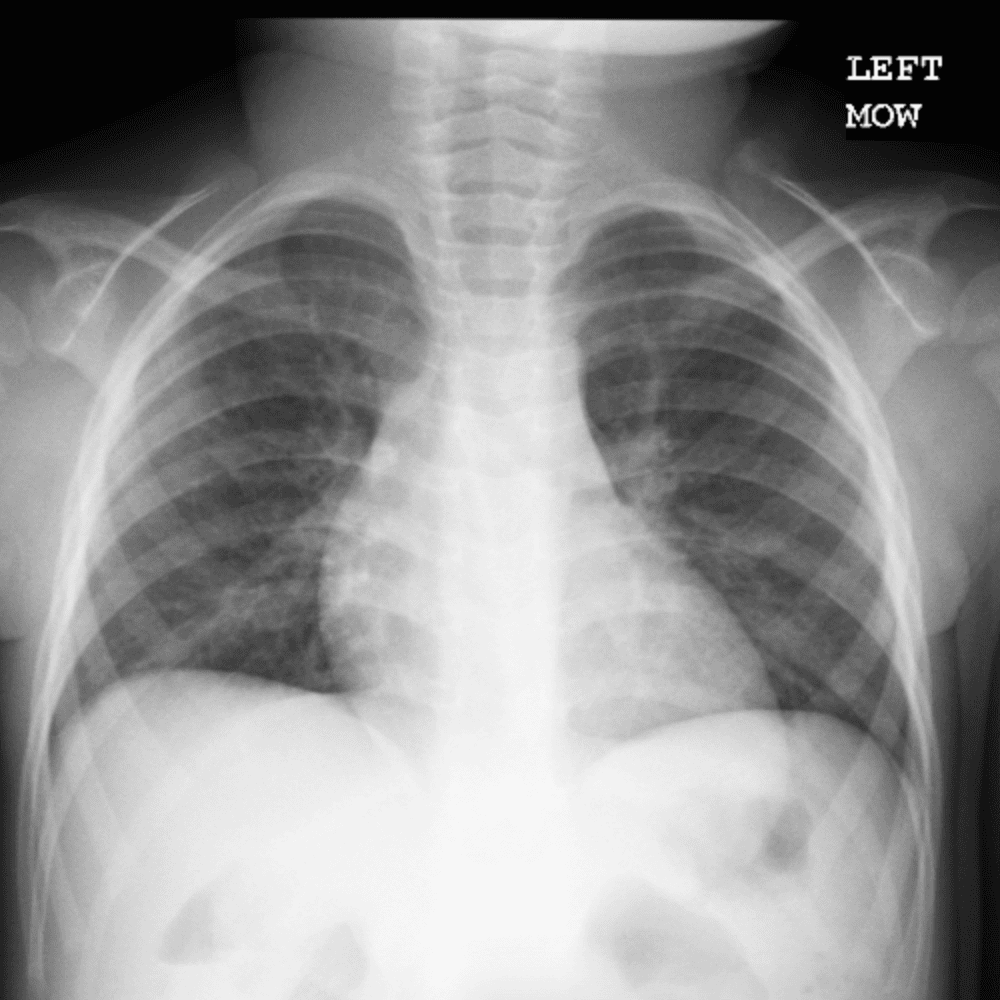

Peds Chest

Practice

Simulates call by including subtle or difficult cases and some normals.

50 cases